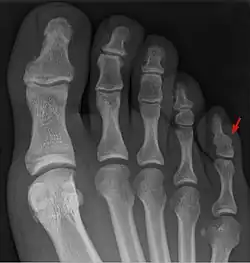

Der Symphalangismus oder die Symphangie (von altgriechisch σύν syn ‚zusammen‘ und φάλαγξ phálanx ‚Reihe‘) ist eine – ausgenommen die Kleinzehe – seltene Fehlbildung mit Verschmelzung (Fusion) zweier Phalangen.[1]

Im Unterschied zur Syndaktylie, bei der die Trennung zwischen benachbarten Fingern beziehungsweise Zehen fehlt oder unvollständig ist,[2] liegt bei der Symphalangie eine knöcherne Verschmelzung zweier Phalangen eines Fingers oder einer Zehe vor, mit Fehlen des betroffenen proximalen oder distalen Finger- bzw. Zehengelenkes.[1]

Eine Symphalangie wird am häufigsten als anatomische Variante (Normvariante) an der Kleinzehe als Fusion von Mittel- und Endphalanx gefunden. Das Vorkommen wird hier mit 40–70 % der Bevölkerung angegeben.[4]

Häufig handelt es sich um einen Zufallsbefund im Röntgenbild

Je nach Ausmaß der Fusion kann zwischen fibröser, knorpeliger und knöcherner Symphalangie unterschieden werden.[13]